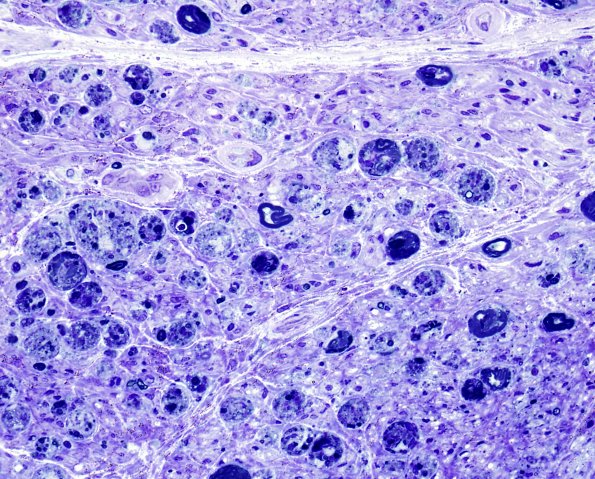

Plastic sections show a variable appearance including marked axonal degeneration. Analysis of this area showed no residual myelinated axons, only degenerated axons. (Plastic sections)